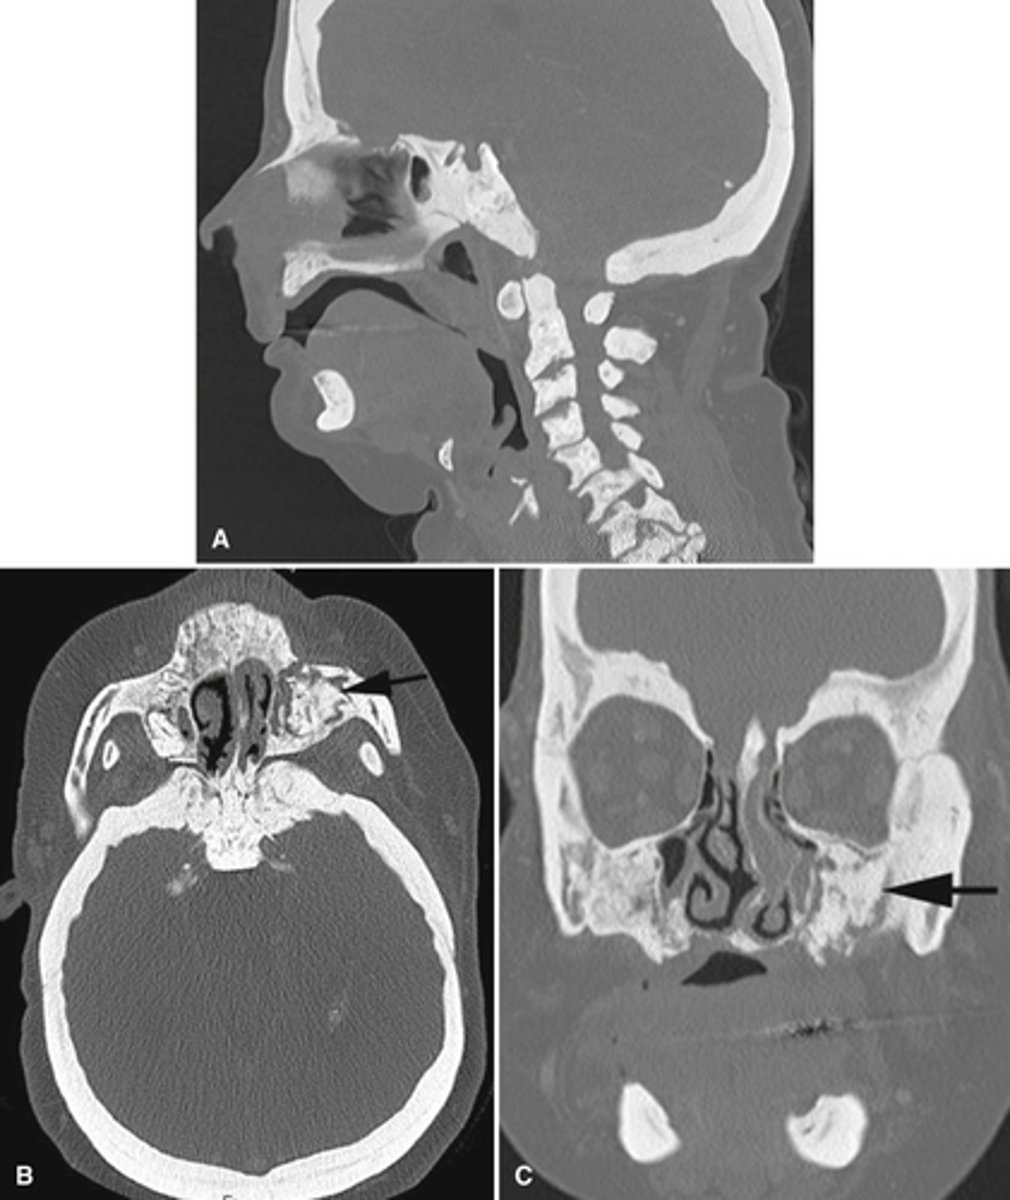

Maxillary sinus perforation causing mucosal thickening.

What does this image show?

Endodontic materials into the maxillary sinus causing mucosal thickening.

What does the image show?